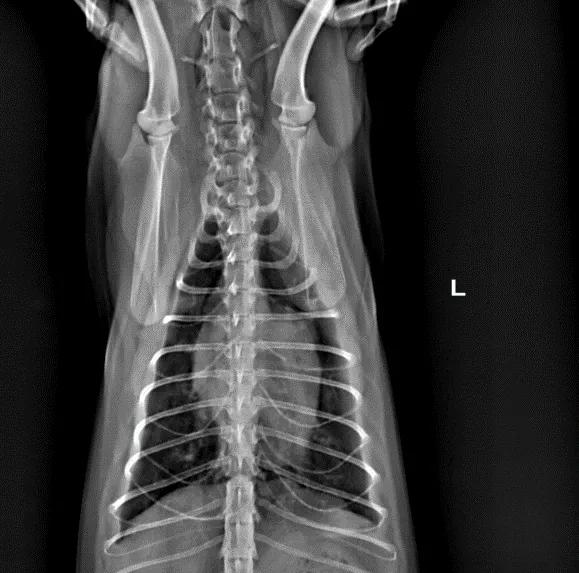

X光检查:右侧位与腹背位显示,肺门处影像学密度上升,心影整体偏大。